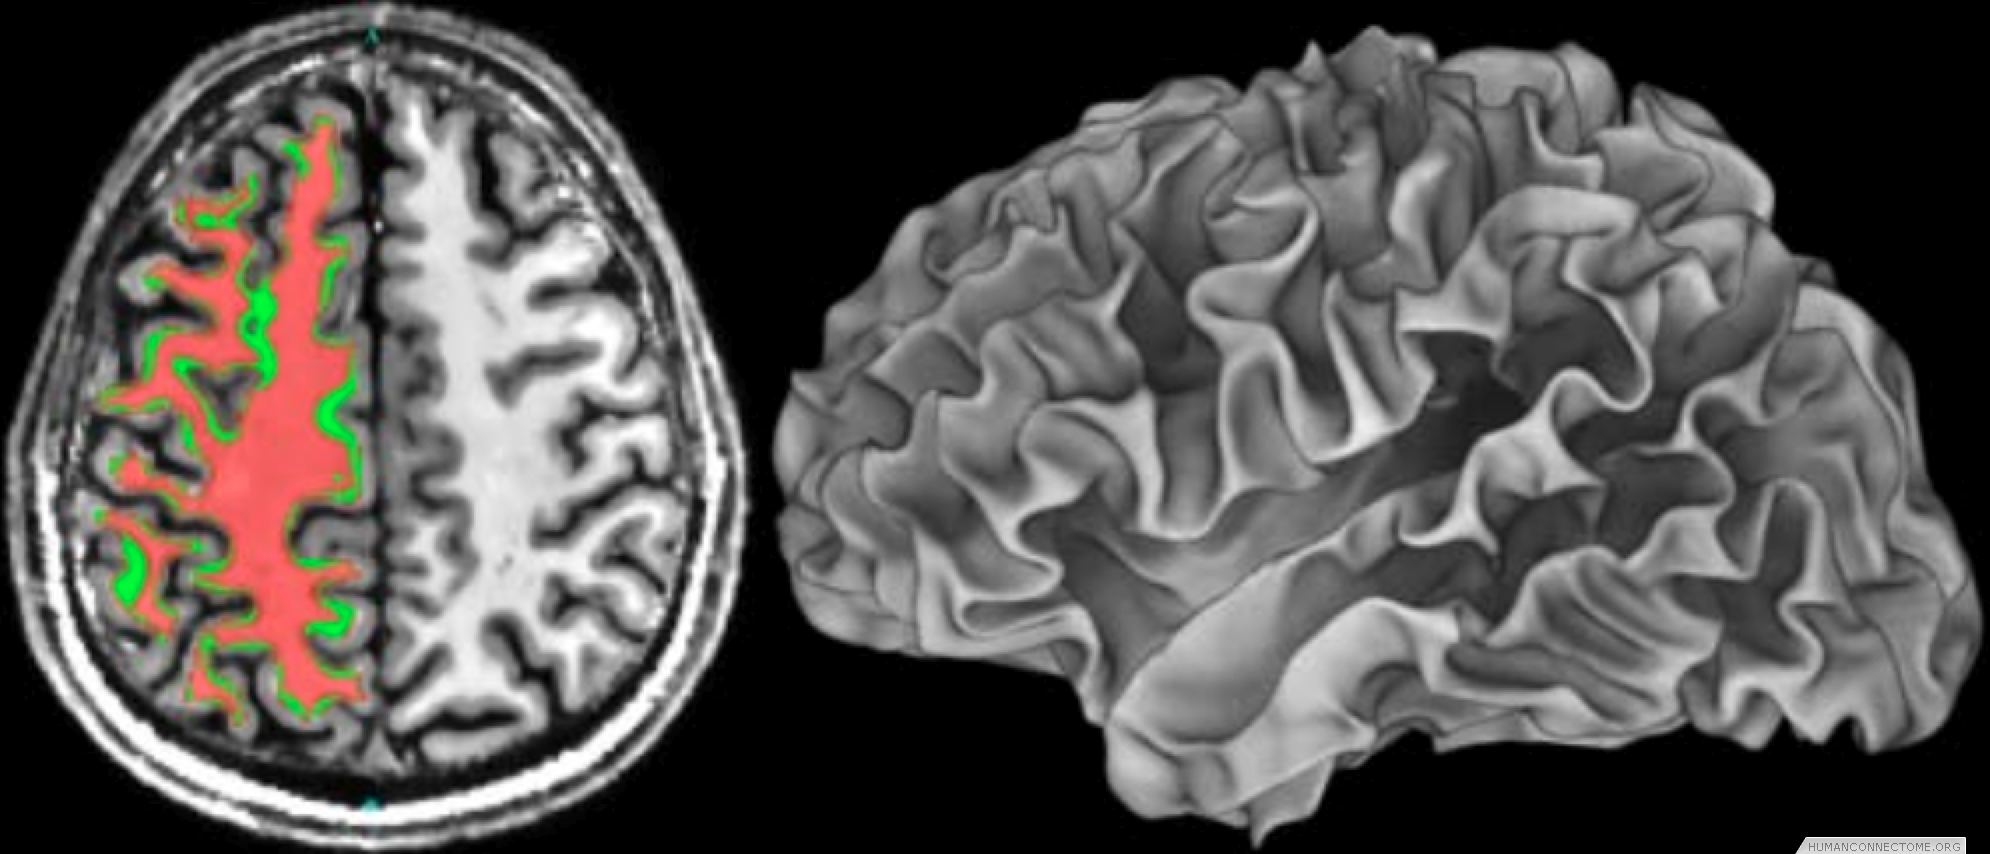

Figure 2: Left: Example T1-weighted image acquired at 7T with white matter segmentation overlaid. Right: White matter surface rendering.

Anatomically constrained analysis and visualization. We are using segmentations and cortical surface models derived from high quality T1-weighted data to underlie much of the analysis and visualization of all modalities. We have established a pipeline that begins with a T1 image and ends with cortical surface models and subcortical segmentation. We are therefore able to combine data across subjects both in 3D standard space and on 2D ‘standard-mesh’ surfaces.